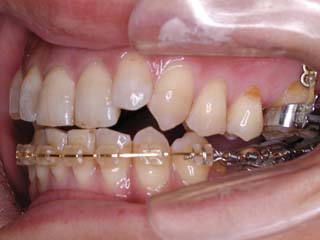

この症例では、上顎にリンガルブラケット矯正装置(Kurz)が用いられています。

この症例では、目的外使用のオーソアンカー SMAPシステム が用いられています。

本症例について検査診断の結果、開咬、叢生、下顎前突傾向を認めました。患者希望を考慮し、治療メカニクスとして、非抜歯配列、上顎のみリンガルブラケット矯正装置、下顎唇側マルチブラケット矯正装置、および、目的外使用のオーソアンカー SMAPシステムを用いることにいたしました。

非抜歯の計画でしたが、下顎臼歯はかなり遠心移動をする予定になっていますので、親不知はあらかじめ抜歯をお願いしました。